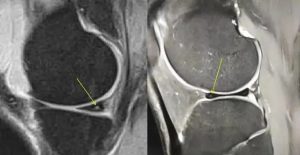

下图:0级

下图I级